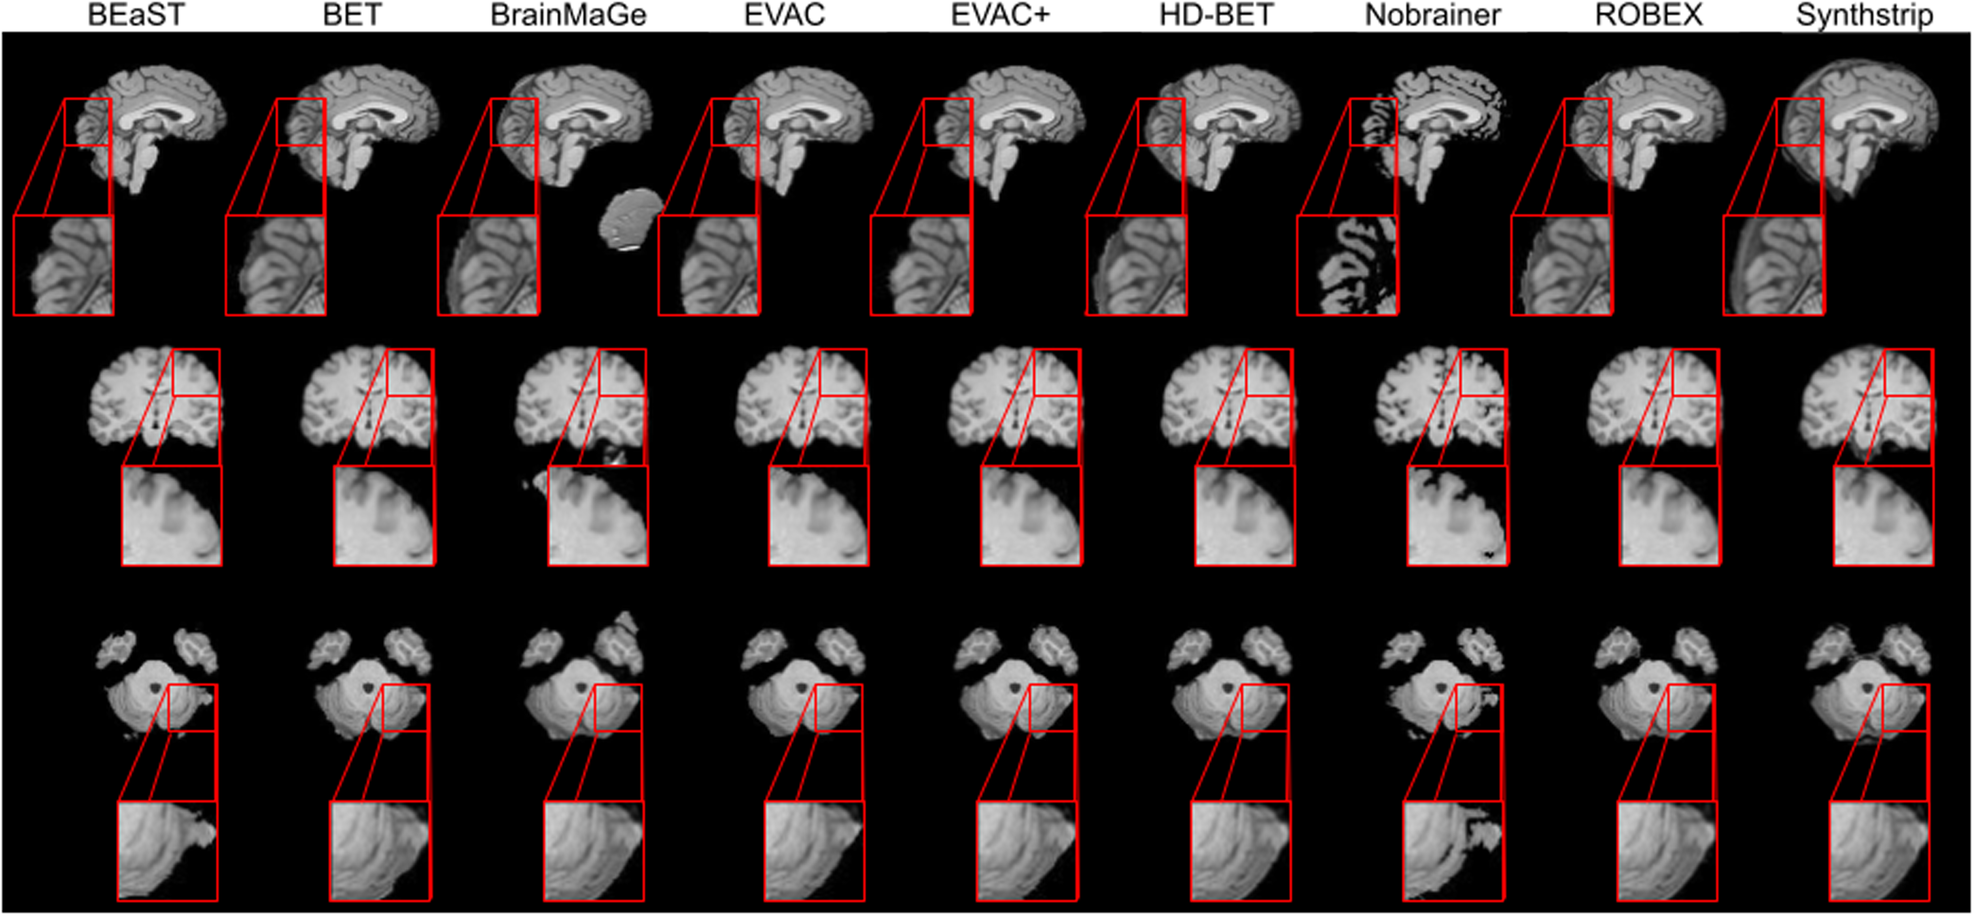

Results show that our approach can achieve competitive segmentation near the boundaries. It is worth emphasizing that this accuracy is from training only on public datasets where a large portion did not have manual annotations.